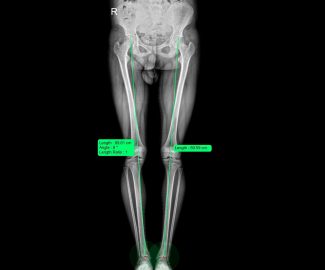

Especialista en diagnóstico por imágenes con más de 25 años de experiencia en el campo del ultrasonido y radiología digital. Trabajamos con equipos de alta tecnología garantizando la calidad y seguridad de nuestros diagnósticos, pues nuestra prioridad es la salud, bienestar y satisfacción de nuestros pacientes.

Sabemos que visitar un centro médico a veces genera nervios. Por eso, hemos creado un ambiente cálido, moderno y 100% seguro para ti. Desde nuestra cómoda sala de espera hasta nuestras áreas de ecografía, mamografía y rayos X, cada rincón está equipado con tecnología de última generación y diseñado para que te sientas en confianza.